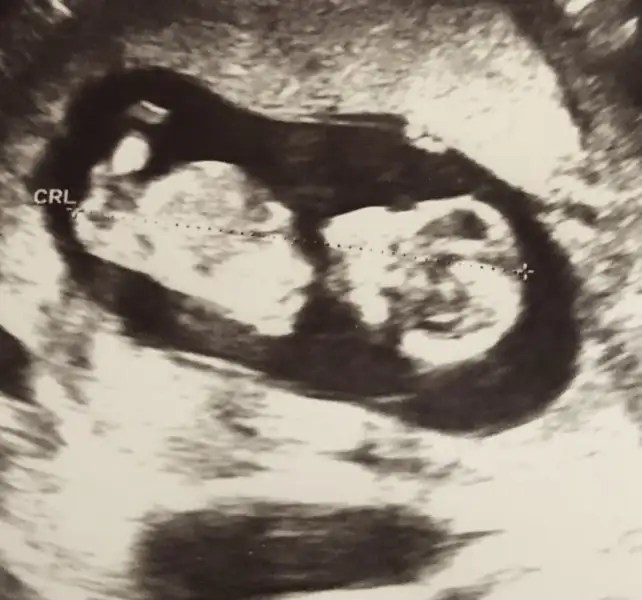

Ilk bebeginmiCanım çok teşekkürler. 3 ayı bitirmiş olacağım bir sonraki kontrolde, doktordan izin alır almaz yürüyüşteyim inşallah.